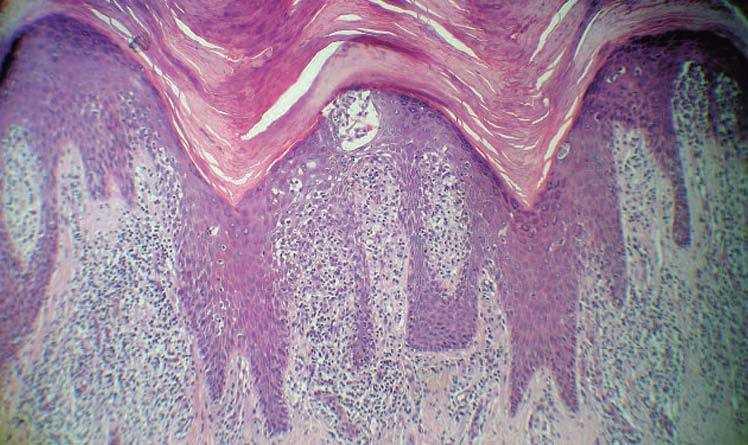

Se realizó un punch biopsia de un borde de la placa de la palma izquierda (figs. 3 y 4).

Figura 3. Tinción hematoxilina-eosina, x100.

El examen histopatológico mostraba una hiperplasia epidérmica psoriasiforme, con un infiltrado en dermis de linfocitos grandes atípicos de núcleo convoluto con figuras de mitosis, exocitosis de linfocitos y exocitosis de linfocitos con formación de abscesos. El estudio inmunohistoquímico mostró positividad para CD3, CD4 y CD8 y fue negativo para CD30.